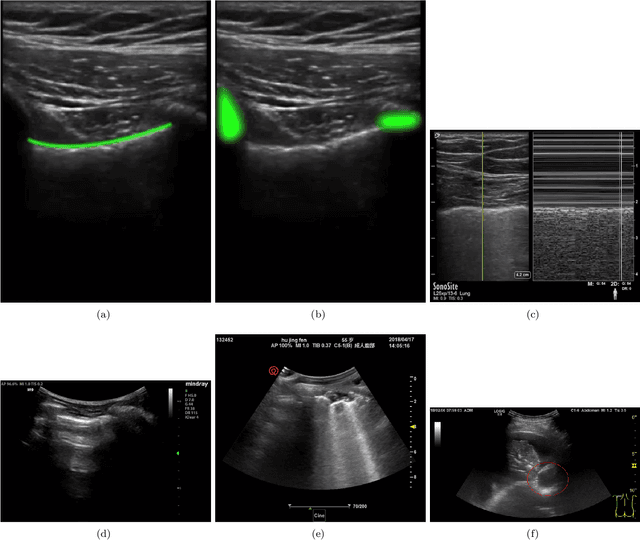

Abstract:Managing fluid balance in dialysis patients is crucial, as improper management can lead to severe complications. In this paper, we propose a multimodal approach that integrates visual features from lung ultrasound images with clinical data to enhance the prediction of excess body fluid. Our framework employs independent encoders to extract features for each modality and combines them through a cross-domain attention mechanism to capture complementary information. By framing the prediction as a classification task, the model achieves significantly better performance than regression. The results demonstrate that multimodal models consistently outperform single-modality models, particularly when attention mechanisms prioritize tabular data. Pseudo-sample generation further contributes to mitigating the imbalanced classification problem, achieving the highest accuracy of 88.31%. This study underscores the effectiveness of multimodal learning for fluid overload management in dialysis patients, offering valuable insights for improved clinical outcomes.

Abstract:The identification of artefacts, particularly B-lines, in lung ultrasound (LUS), is crucial for assisting clinical diagnosis, prompting the development of innovative methodologies. While the Cauchy proximal splitting (CPS) algorithm has demonstrated effective performance in B-line detection, the process is slow and has limited generalization. This paper addresses these issues with a novel unsupervised deep unfolding network structure (DUCPS). The framework utilizes deep unfolding procedures to merge traditional model-based techniques with deep learning approaches. By unfolding the CPS algorithm into a deep network, DUCPS enables the parameters in the optimization algorithm to be learnable, thus enhancing generalization performance and facilitating rapid convergence. We conducted entirely unsupervised training using the Neighbor2Neighbor (N2N) and the Structural Similarity Index Measure (SSIM) losses. When combined with an improved line identification method proposed in this paper, state-of-the-art performance is achieved, with the recall and F2 score reaching 0.70 and 0.64, respectively. Notably, DUCPS significantly improves computational efficiency eliminating the need for extensive data labeling, representing a notable advancement over both traditional algorithms and existing deep learning approaches.

Abstract:In the context of lung ultrasound, the detection of B-lines, which are indicative of interstitial lung disease and pulmonary edema, plays a pivotal role in clinical diagnosis. Current methods still rely on visual inspection by experts. Vision-based automatic B-line detection methods have been developed, but their performance has yet to improve in terms of both accuracy and computational speed. This paper presents a novel approach to posing B-line detection as an inverse problem via deep unfolding of the Alternating Direction Method of Multipliers (ADMM). It tackles the challenges of data labelling and model training in lung ultrasound image analysis by harnessing the capabilities of deep neural networks and model-based methods. Our objective is to substantially enhance diagnostic accuracy while ensuring efficient real-time capabilities. The results show that the proposed method runs more than 90 times faster than the traditional model-based method and achieves an F1 score that is 10.6% higher.

Abstract:Studies have proved that the number of B-lines in lung ultrasound images has a strong statistical link to the amount of extravascular lung water, which is significant for hemodialysis treatment. Manual inspection of B-lines requires experts and is time-consuming, whilst modelling automation methods is currently problematic because of a lack of ground truth. Therefore, in this paper, we propose a novel semi-supervised learning method for the B-line detection task based on contrastive learning. Through multi-level unsupervised learning on unlabelled lung ultrasound images, the features of the artefacts are learnt. In the downstream task, we introduce a fine-tuning process on a small number of labelled images using the EIoU-based loss function. Apart from reducing the data labelling workload, the proposed method shows a superior performance to model-based algorithm with the recall of 91.43%, the accuracy of 84.21% and the F1 score of 91.43%.

Abstract:In the field of biomedical imaging, ultrasonography has become increasingly widespread, and an important auxiliary diagnostic tool with unique advantages, such as being non-ionising and often portable. This article reviews the state-of-the-art in medical ultrasound image computing and in particular its application in the examination of the lungs. First, we review the current developments in medical ultrasound technology. We then focus on the characteristics of lung ultrasonography and on its ability to diagnose a variety of diseases through the identification of various artefacts. We review medical ultrasound image processing methods by splitting them into two categories: (1) traditional model-based methods, and (2) data driven methods. For the former, we consider inverse problem based methods by focusing in particular on ultrasound image despeckling, deconvolution, and line artefacts detection. Among the data-driven approaches, we discuss various works based on deep/machine learning, which include various effective network architectures implementing supervised, weakly supervised and unsupervised learning.